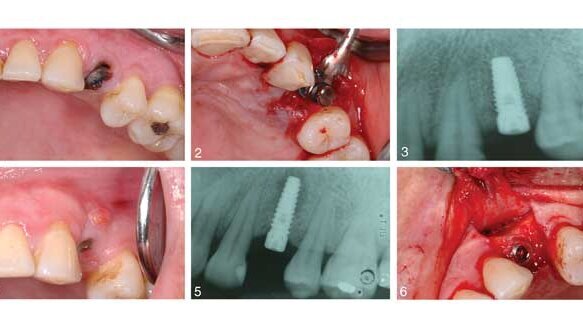

A 43-year-old female presenting with a symptomatic left, first premolar was a candidate for dental implant treatment and scheduled for an immediate implant placement following tooth extraction. After surgery she was prescribed antibiotics. She was seen three months later due to pain at the implant site, which revealed a sinus tract related to the implant. Additionally, there was a “soft spot” due to edema and bone loss. She was prescribed another course of antibiotics and returned in four days. At that time, a tetracycline paste was created and placed on the defect and around the implant for three minutes, then removed. In two months a transitional crown was placed, with placement of the final six months later. At the subsequent one-month, two-month, six-month, one-year and five-year appointments, no pain was reported, and complete bone fill in to the previous lesion area was stable.

IPL is a rare disorder, affecting approximately 0.26 percent of the population receiving implants. There are varying reasons for its cause, and it can sometimes be misdiagnosed or confused with retrograde peri-implantitis. The combination of antibiotics and GBR principals has shown to be an effective way of treating IPL, keeping the implant intact, and creating a complete bone fill at the lesion site. This case study appears to be the first of its kind, so further research will be needed to confirm findings.